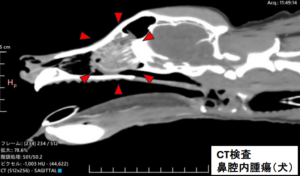

つまり、鼻腔内の腫瘍性疾患や歯科疾患、感染症、止血異常など、多種多様な病気が潜んでいる可能性があります。

例えば、高齢のワンちゃんでは、鼻出血の約50%以上で鼻腔内腫瘍であったという報告がある一方で、歯周病が鼻出血の原因になることも多々あります。

鼻腔内は鼻骨などの硬い骨に囲まれた空間であることから、外から異常に気付くことが難しい部位の一つです。

当院ではCT検査や内視鏡カメラ、血液凝固分析装置などの診断・検査機器を用いて、鼻血で来院されたワンちゃん・ネコちゃんの診察・ご相談に総合的に応じています。📷